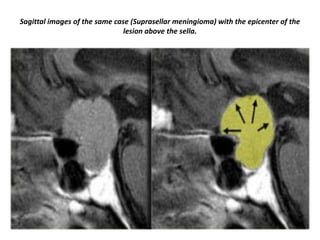

Supra-sellar meningioma with the epicenter of the lesion above the sella.

Sagittal images of the same case (Suprasellar meningioma) with the epicenter of the

lesion above the sella.